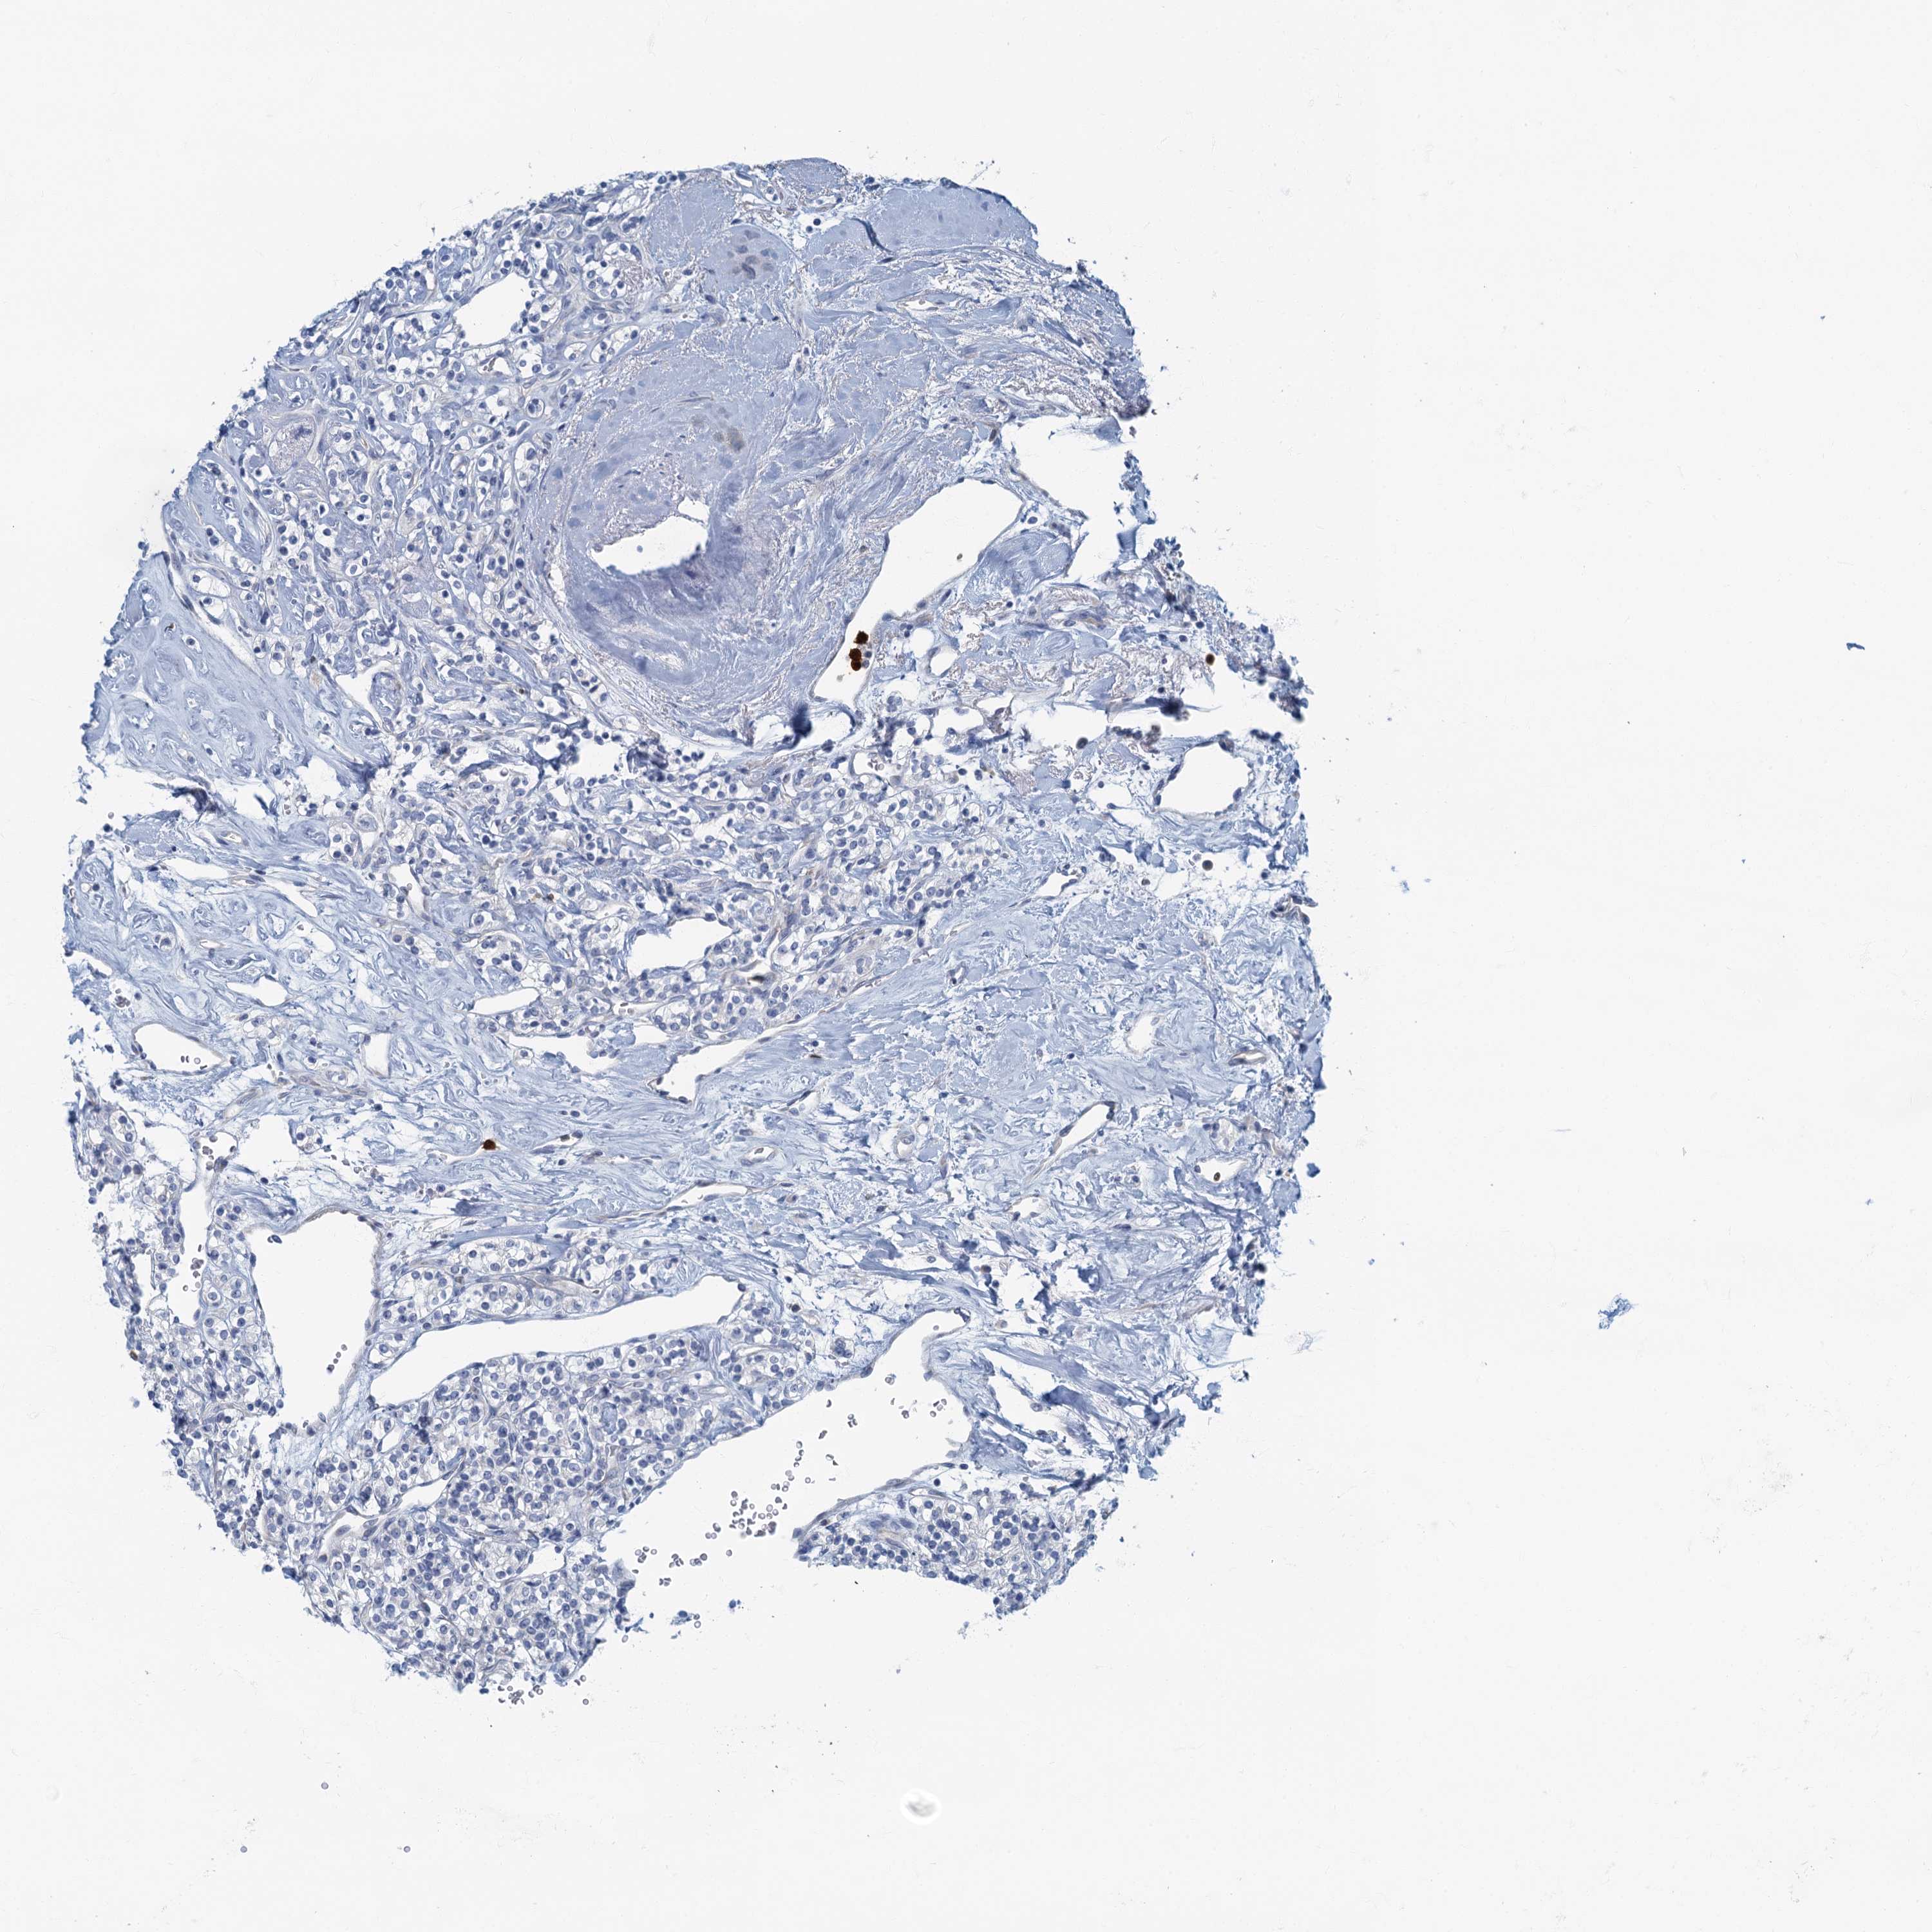

KIDNEY RENAL CLEAR CELL CARCINOMA (TCGA) - Interactive survival scatter ploti

The Survival Scatter plot shows the clinical status (i.e. dead or alive) for all individuals in the patient cohort, based on the same data that underlies the corresponding Kaplan-Meier plots. Patients that are alive at last time for follow-up are shown in blue and patients who have died during the study are shown in red.

The x-axis shows the expression levels (FPKM) of the investigated gene in the tumor tissue at the time of diagnosis. The y-axis shows the follow-up time after diagnosis (years). Both axes are complimented with kernel density curves demonstrating the data density over the axes. The top density plot shows the expression levels (FPKM) distribution among dead (red) and alive patients (blue). The right density plot shows the data density of the survived years of dead patients with high and low expression levels respectively, stratified using the cutoff indicated by the vertical dashed line through the Survival Scatter plot. This cutoff is automatically defined based on the FPKM cutoff that minimizes the p-score. The cutoff can be changed by dragging the vertical line or by entering a cutoff value in the square labeled "Current cut-off".

Under the Survival Scatter plot the p-score landscape (black curve; left axis) is shown together with dead median separation (red curve; right axis). Dead median separation is the difference in median mRNA expression between patients who have died with high and low expression, respectively. It is calculated as follows: median FPKM expression of dead patients with high expression - median FPKM expression of dead patients with low expression. This is intended to aid the user in visually exploring custom cutoffs and the associated p-scores and dead median separation.

Individual patient data is displayed and can be filtered by clicking on one or more of the category buttons on the top of the page. Categories describing expression level and patient information include: high, low, alive, dead, female, male and tumor stages. The scale of the x-axis can be toggled between linear and log-scale by clicking on the "x log" button. Mouse-over function shows TCGA ID, patient information and mRNA expression (FPKM) for each patient.

& Survival analysisi

Kaplan-Meier plots summarize results from analysis of correlation between mRNA expression level and patient survival. Patients were divided based on level of expression into one of the two groups "low" (under cut off) or "high" (over cut off). X-axis shows time for survival (years) and y-axis shows the probability of survival, where 1.0 corresponds to 100 percent.

ANKDD1A is potential prognostic, high expression is unfavorable in Kidney Renal Clear Cell Carcinoma (TCGA)

Best expression cut offi

Based on the FPKM value of each gene, patients were classified into two groups and association between prognosis (survival) and gene expression (FPKM) was examined. The best expression cut-off refers the FPKM value that yields maximal difference with regard to survival between the two groups at the lowest log-rank P-value. Best expression cut-off was selected based on survival analysis .

When clicking on this number, the vertical dashed line indicating cut-off, the interactive survival plot, and the Kaplan-Meier curve will be adjusted to show results based on the best expression cut-off.

: 1.4

TCGA RNA samplesi

RNA-seq data is reported as average FPKM (number Fragments Per Kilobase of exon per Million reads), generated by the The Cancer Genome Atlas (TCGA) .

Normal distribution across the dataset is visualized with box plots, shown as median and 25th and 75th percentiles. Points are displayed as outliers if they are above or below 1.5 times the interquartile range. FPKM values of the individual samples are presented next to the box plot.

Average pTPM 1.9

Number of samples 521